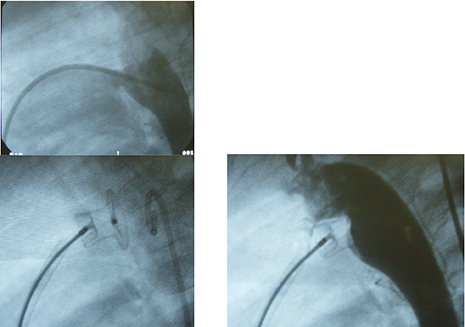

このカテ室で、年齢1才5カ月、体重9.5kgの女児、3.5mm径のPDAを、コイル3個で閉鎖した時の画像です。